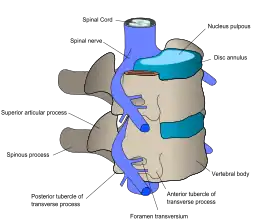

The lumbar (or lower back) region is made up of five vertebrae (L1–L5), sometimes including the sacrum. In between these vertebrae are fibrocartilaginous discs, which act as cushions, preventing the vertebrae from rubbing together while at the same time protecting the spinal cord. Nerves come from and go to the spinal cord through specific openings between the vertebrae, providing the skin with sensations and messages to muscles. Stability of the spine is provided by the ligaments and muscles of the back and abdomen. Small joints called facet joints limit and direct the motion of the spine.[32]

The multifidus muscles run up and down along the back of the spine, and are important for keeping the spine straight and stable during many common movements such as sitting, walking and lifting.[12] A problem with these muscles is often found in someone with chronic low back pain, because the back pain causes the person to use the back muscles improperly in trying to avoid the pain.[33] The problem with the multifidus muscles continues even after the pain goes away, and is probably an important reason why the pain comes back.[33] Teaching people with chronic low back pain how to use these muscles is recommended as part of a recovery program.[33]

An intervertebral disc has a gelatinous core surrounded by a fibrous ring.[34] When in its normal, uninjured state, most of the disc is not served by either the circulatory or nervous systems – blood and nerves only run to the outside of the disc.[34] Specialized cells that can survive without direct blood supply are in the inside of the disc.[34] Over time, the discs lose flexibility and the ability to absorb physical forces.[26] This decreased ability to handle physical forces increases stresses on other parts of the spine, causing the ligaments of the spine to thicken and bony growths to develop on the vertebrae.[26] As a result, there is less space through which the spinal cord and nerve roots may pass.[26] When a disc degenerates as a result of injury or disease, the makeup of a disc changes: blood vessels and nerves may grow into its interior and/or herniated disc material can push directly on a nerve root.[34] Any of these changes may result in back pain.[34]